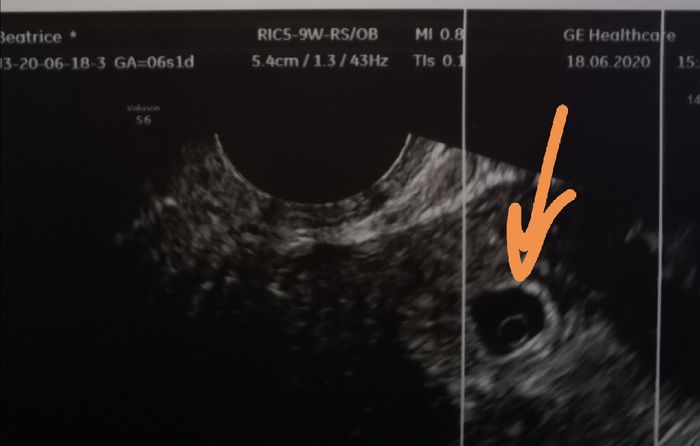

Da Beatrice , Il 18 Giugno 2020 alle 15:58

Buongiorno future mamme! Oggi ho scoperto il mio positivo e secondo l’app la DPP è 04/02/2021. Sono già mamma di Giorgia, 1 anno, e non vedevamo l’ora di darle un...